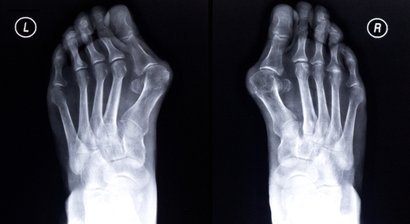

Fußchirurgie

Beschwerden und Probleme im Bereich vom Fuß sind entweder angeboren oder erworben , beispielsweise durch das Tragen von zu engem Schuhwerk wie etwa in vielen Fällen eines Hallux valgus , oder durch andere Umwelteinflüsse. Viele Fehlstellungen vom Fuß können in der Ordinati...